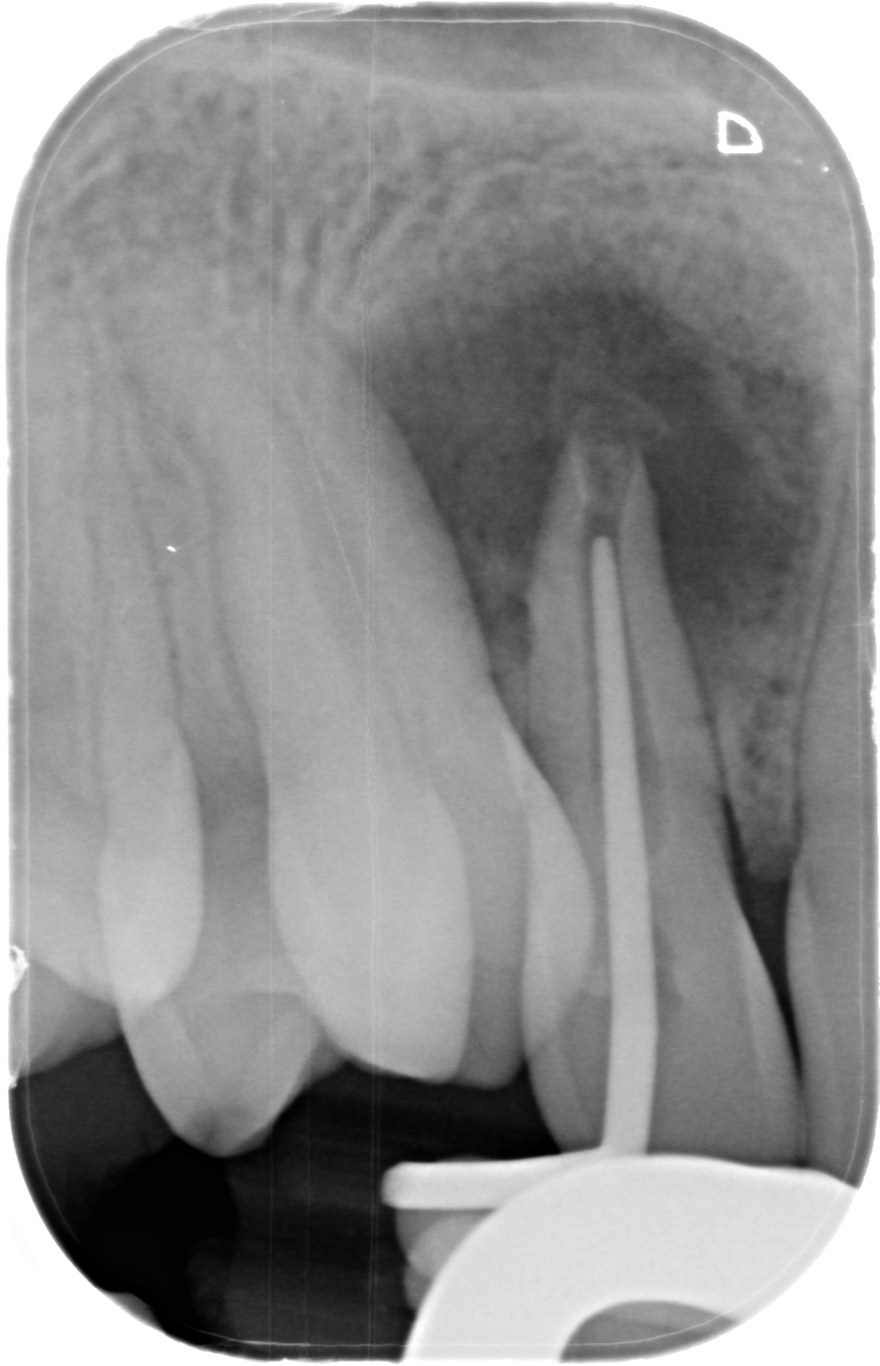

Implantes e implantoprótesis en Segovia

Es la especialidad dedicada a reponer los dientes perdidos/ausentes mediante la colocación de un implante, un “tornillo” de titanio anclado al hueso, y que una vez se ha osteointegrado (soldado al hueso), permite colocar una corona protésica atornillada directamente al implante.

En Clidentse contamos con el Dr. Ángel Silmi para esta especialidad, que es sin duda la opción ideal y más conservadora para reponer los dientes perdidos y/o ausentes. De otra forma, la prótesis fija convencional sobre

diente exige tallar (desgastar) los dientes adyacentes a la ausencia, los cuales hacen de pilares de un puente de 3 piezas para reponer el diente perdido. Con los implantes dentales, esta antigua opción terapéutica fija está desaconsejada. Hoy día se tiende a hacer una Odontología Mínimamente Invasiva. Y tallar los dientes supone un tratamiento excesivamente traumático y debilitante. La resistencia de los dientes está relacionada directamente con la cantidad de diente sano remanente.